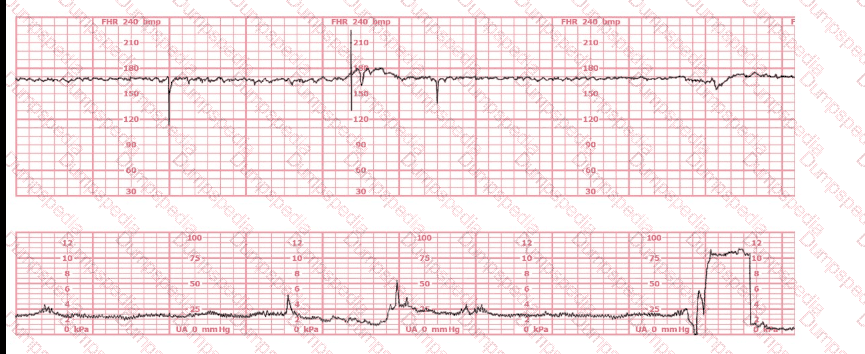

A nulliparous woman at term presents with leaking fluid. Rupture of membranes confirmed. After 6 hours she is completely dilated, +2 station, has been pushing 2 hours with oxytocin at 10 mU/min. The fetal tracing is shown. What is the next step in management?

(Full question statement)